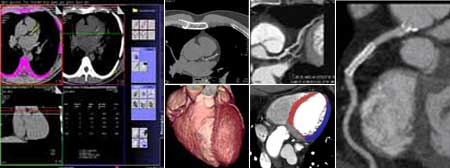

Koronarna CT angiografija

Kardiovaskularne bolesti su ubica broj jedan u današnjem svijetu i odnose svake godine više života nego sve maligne bolesti zajedno. Koronarna bolest je najčešće uzrokovana aterosklerozom (stvaranjem plakova u zidu krvnih žila uzrokojući njihvo suženje). Donedavno, nije postojao neinvazivni način da se direktno analiziraju koronarne arterije na prisustvo aterosklerotskih promjena. Razvoj tehnologije višeslojnog CT-a (MSCT/MDCT) omogućio je detaljno trodimenzionalno prikazivanje kucajućeg srca u toku jednog zadržavanja daha. U našem dijagnostičkom centru nudimo ovu tehniku pregleda koronarnih arterija, na multi-slice aparatu, s najmodernijim softverom i minimalnom dozom zračenja.

Šta je CT koronarografija?

To je metoda prikaza malih arterija koje hrane  srčani mišić, upotrebom CT skenera, koji prikazuje protok krvi u koronarnim arterijama i kompjuterskog softvera da bi se dobio odgovarajući trodimenzionalni prikaz. CT angiografija je neinvazivni način da se prikažu zidovi koronarnih arterija I nadju eventualni aterosklerotski plakovi, što pomaže liječniku u odredjivanju rizika srčanog udara.